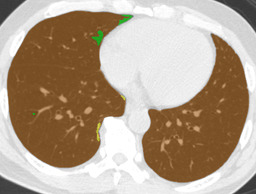

Ground truth Supervised only Proposed (λ=0.1𝜆0.1\lambda=0.1) Proposed (λ=1𝜆1\lambda=1)

CON \blacksquare

Refer to caption Refer to caption Refer to caption Refer to caption

0.839 0.868 0.824

Figure 4: Average results and dice coefficients for each DLD pattern. Automated segmentation results are superimposed with colors. For each DLD pattern, the slice that gave the median dice coefficient for the proposed method with λ=0.1𝜆0.1\lambda=0.1 was chosen to represent the average result. Note that although CNN performed multi-class segmentation, only one DLD pattern per slice was taken into account for the evaluation.